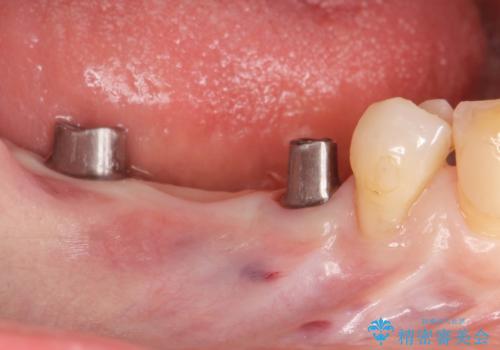

失った奥歯をインプラントで機能回復

- 3本失った奥歯の機能回復するために、インプラント治療を希望され来院されました。

よりしっかりと噛むことのできるインプラントによる治療を進めていくこととなりました。

- 110万円(インプラント×2・チタンカスタムアバットメント×2・ジルコニアクラウン×3・仮歯×3)費用は治療当時の料金となります